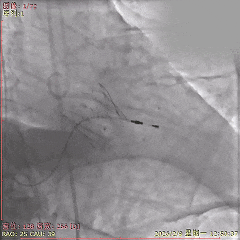

术中影像

初始造影确定无冠窦

瓣膜瓣下定位释放,全展开后位置良好

左侧位造影,瓣膜位置可,选择脱钩

脱钩后造影,瓣膜位置可,无反流